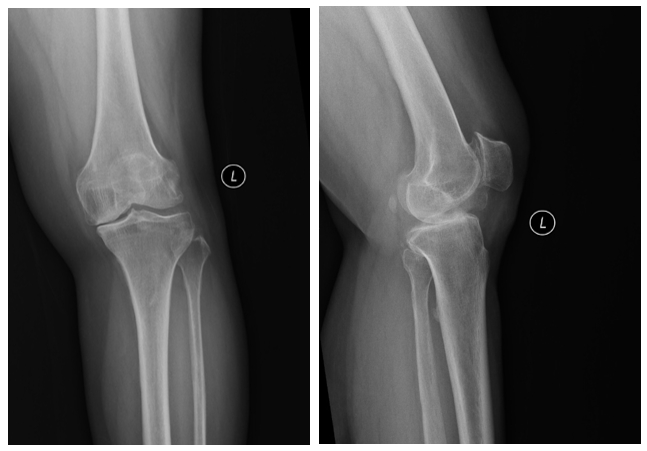

患者是一位57岁的女性,双膝关节疼痛3年,近3个月加重,左膝关节较为严重,无明显肿胀,膝关节内侧缘压痛阳性,髌骨研磨试验阳性,膝关节侧方应力试验、前后抽屉试验阴性。经诊断,确定为前内侧骨性关节炎,谭红略主任团队为患者制定了微创的保膝治疗方案——膝关节单髁置换术。

术前